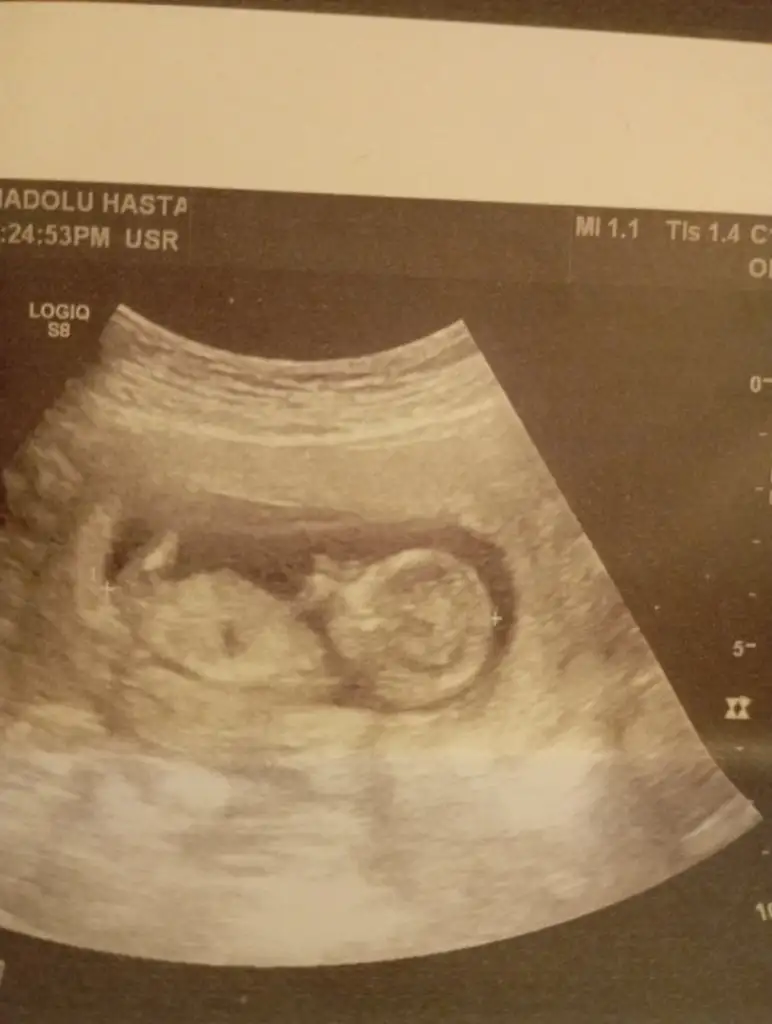

Meraba kızlar 13 haftalık ultrson resmi doktor mınık çıkıntı gördüğünü söyledi fakat çıkıntı üzüntü değil dedı gölge var dedı net ne kız nede net erkek dedı sadece erkek olabilir 1-2 hafta sonra net bellı olcak bırde siz balar mısınınz çok heyecanlıyım:) ıkılı test ıcın ense kalınlığna bakılınca orda çıkıntı yok kız dediler kafam çok karıstı

Valla bende esımde oğlum da kız hissediyoruz radyoloji uzmanı ense ölcüsü kız dedı çıkıntı sivri değil minik dedı erkek olsa 13 de sivri belirgin çıkıntı olur dedı bızım doktor emin olamadı sadece tahminde bulundu pazarteai gidicem inşallah net kız oldğu çıkar dedğinz gibi aay çok heyecanladnım:)